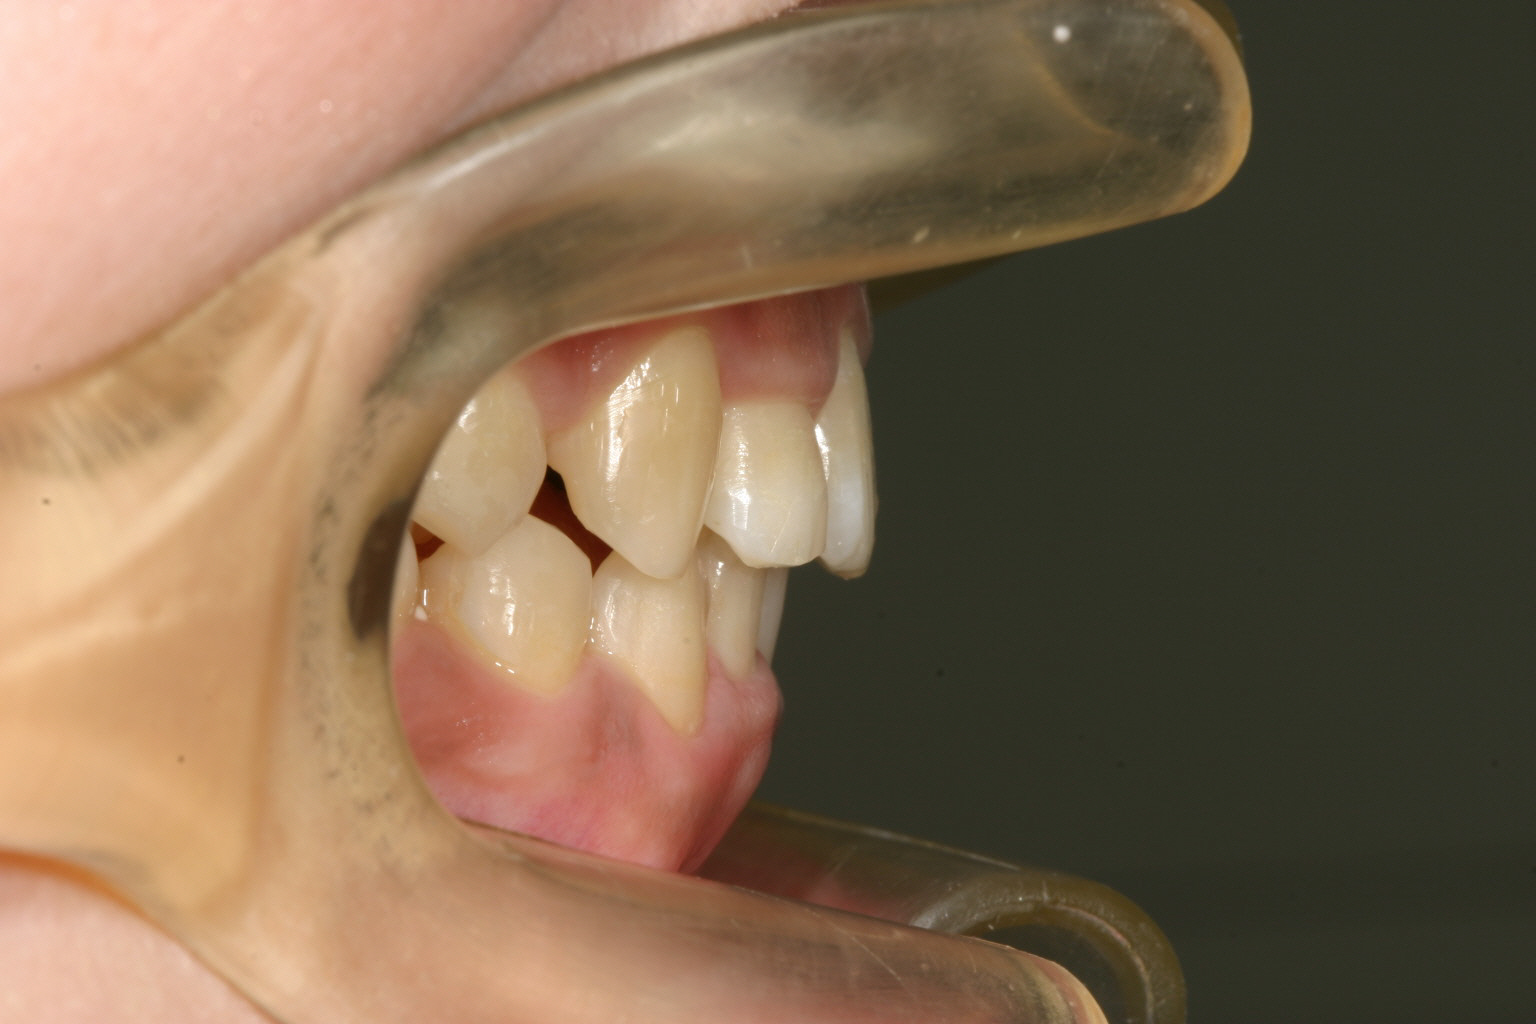

症面観です。 見栄えは悪いですが、ゆっくりとした力がかかるため歯には優しい装置です。

オーバージェットも綺麗に改善しました。